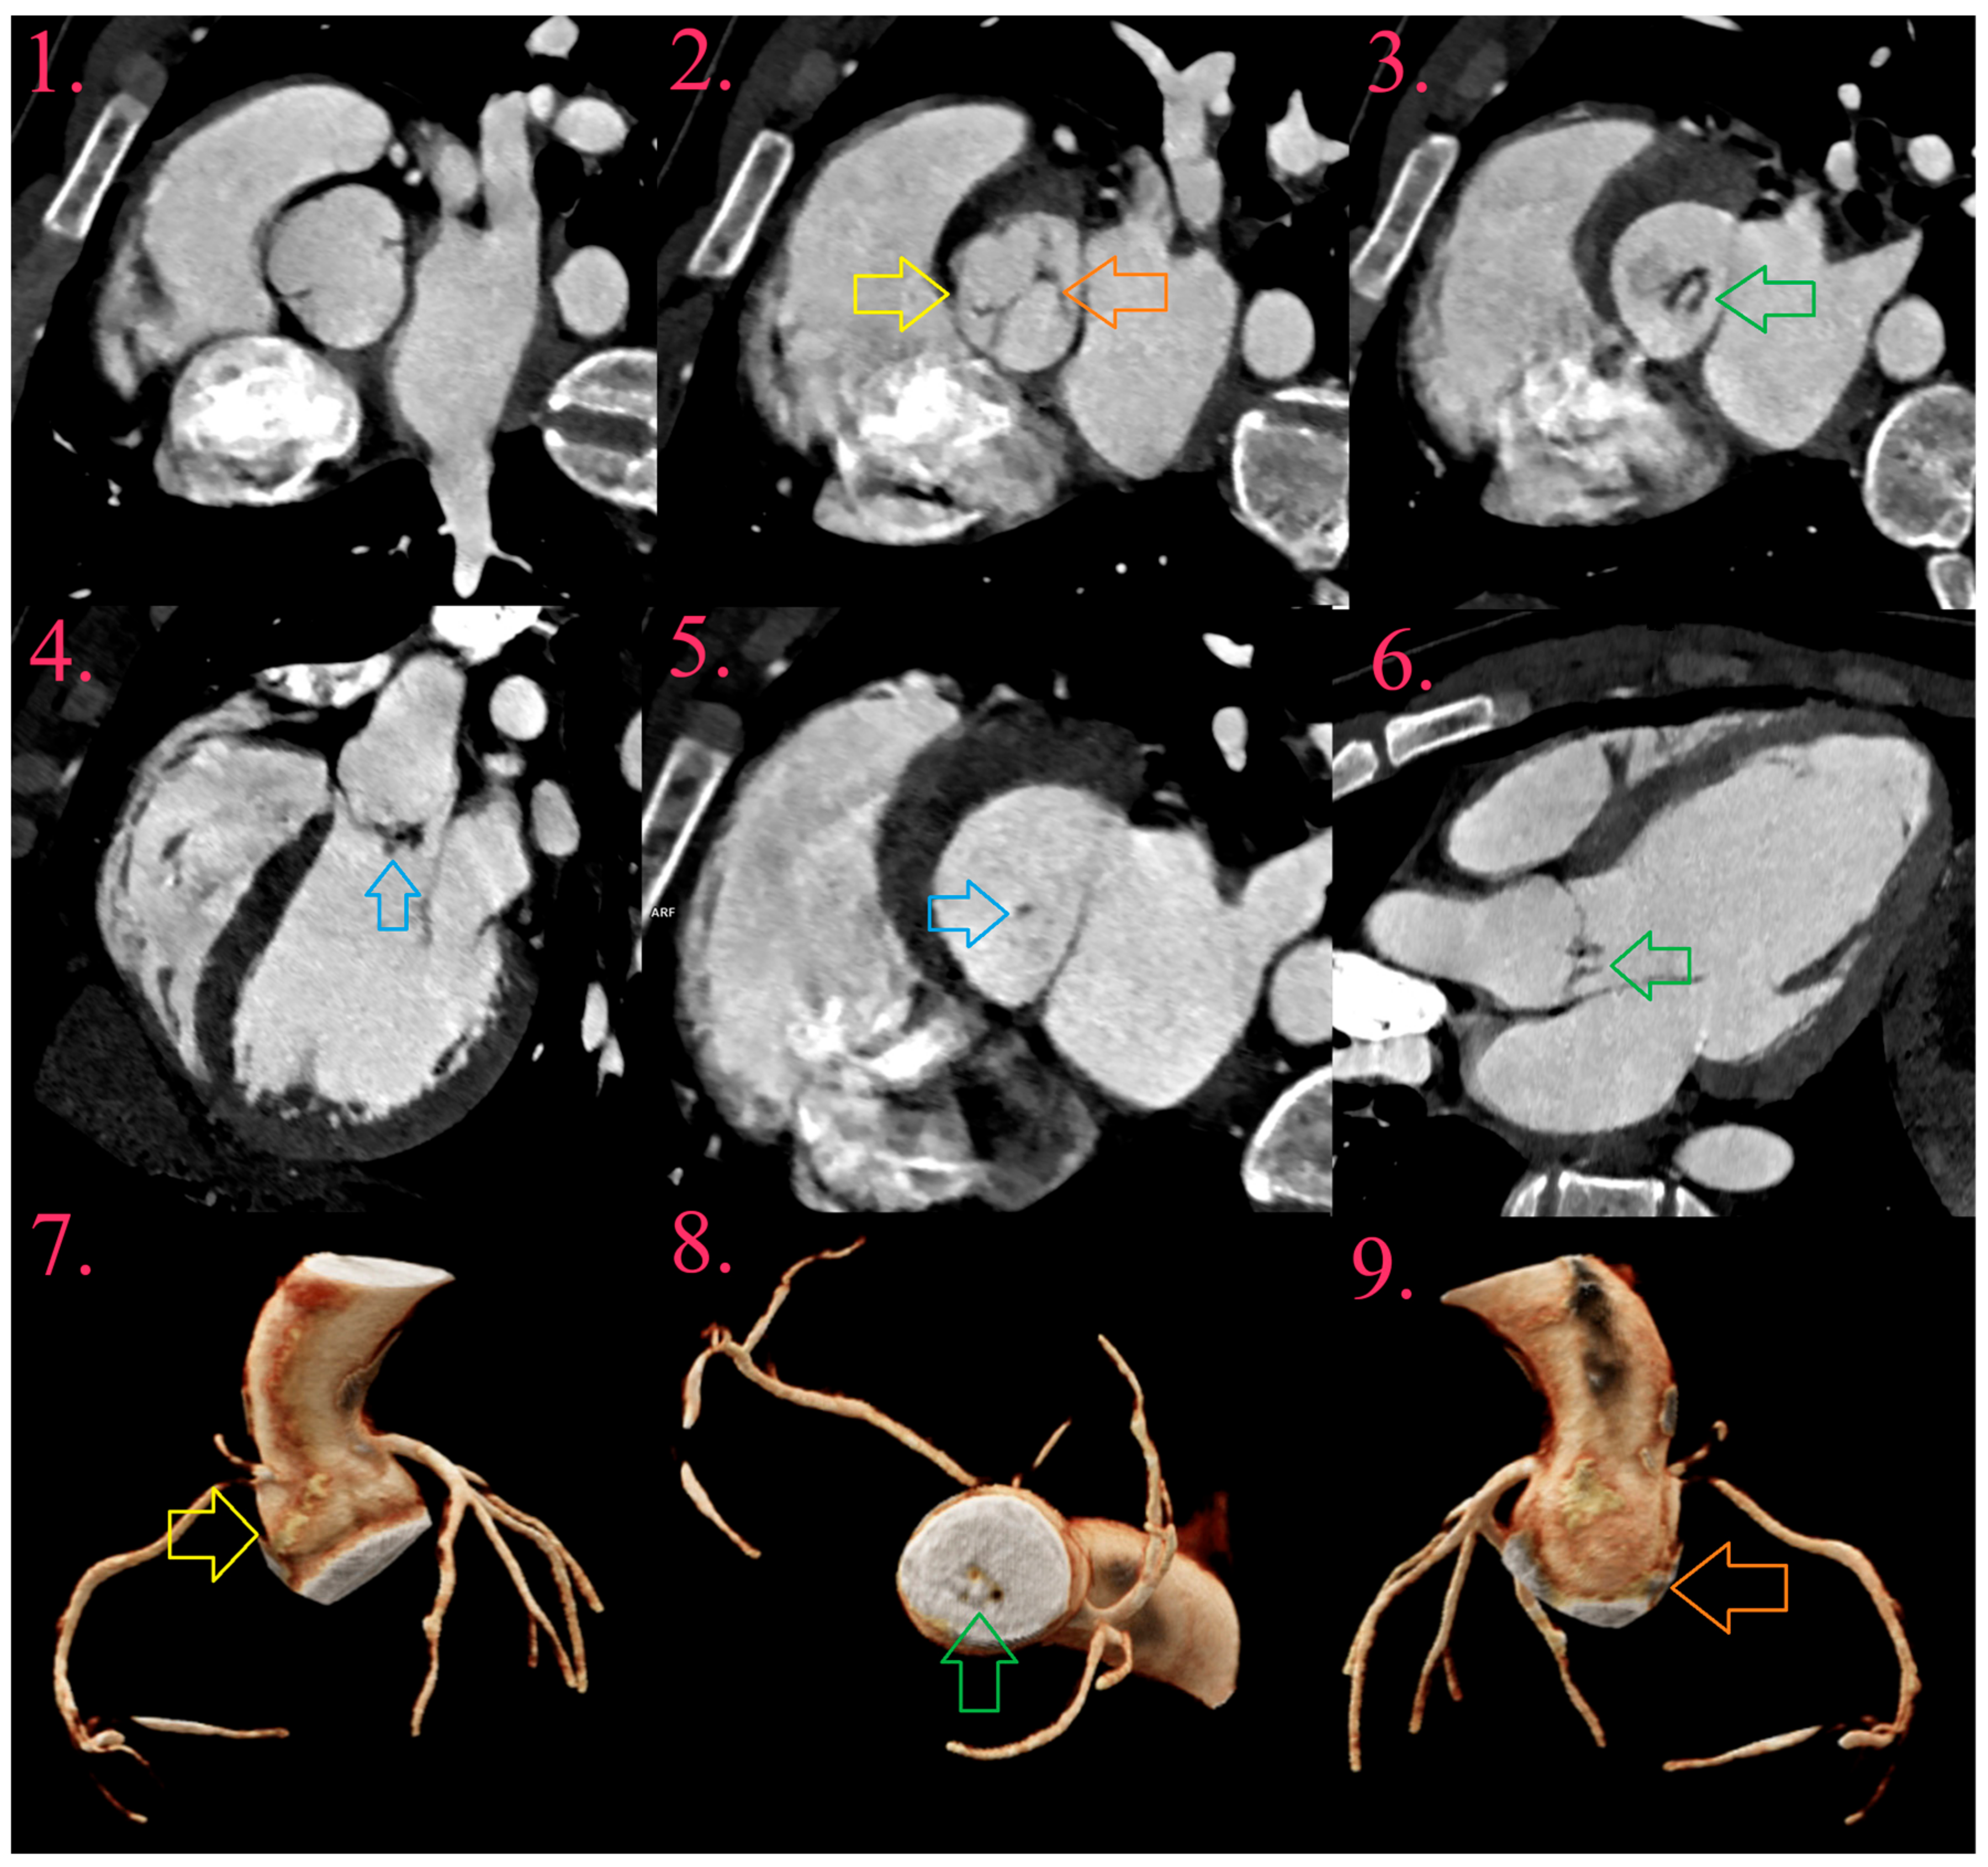

Figure 2.

IE of fused bicuspid aortic valve (BAV) in young male patient (Image 1), with fused right and left coronary cusps (Image 2 and Image 7, yellow arrow) and non-coronary cusp (Image 2 and Image 9, orange arrow), with aneurysm development at its bottom (Image 3, Image 6, and Image 8, green arrow). There is uniform thickening of aneurysm, with small vegetation (Image 4 and Image 5, blue arrow).

6.2. Aneurysms

Aneurysms appear as saccular outpouching of leaflets with loss of homogenous curvature (Figure 1 and Figure 2) [32,63]. They could be the only present IE-related lesion and are considered as a late complication. All aneurysms are localized in the direction of blood flow, and most often on the mitral valve, while the aortic and tricuspid valves are less common. Histologically, aneurysms consist of connective tissue containing remnants of the valve, lined with organized or fresh thrombotic masses. Often the tip of the aneurysm can perforate leading to worsening regurgitation [34,35,40].